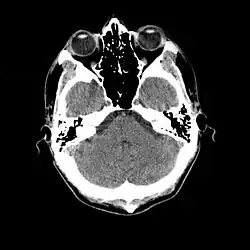

Coupe de scanner cérébral, normal au cours d'une méningite.

Une ponction veineuse est effectuée afin de rechercher des marqueurs d'inflammation (élévation de la CRP, hyperleucocytose) et d'effectuer une hémoculture[10],[26].

L'examen complémentaire essentiel à l'identification d'une méningite est l'analyse du liquide cérébrospinal obtenu par ponction lombaire[27]. Toutefois une telle ponction est contre-indiquée en cas de masse cérébrale (tumeur, abcès) ou d'hypertension intracrânienne, pouvant entraîner un engagement cérébral. En cas de situation à risque (traumatisme crânien, déficit immunitaire, signe neurologique focal, signe clinique d'hypertension intracrânienne), une imagerie cérébrale préalable est recommandée, avec un scanner ou une IRM[10],[26],[28]. C'est une situation concernant potentiellement environ 45 % des cas adultes[9]. Lorsqu'une imagerie est effectuée avant la ponction ou que celle-ci se montre difficile à réaliser, il est suggéré d'administrer un traitement antibiotique immédiatement afin de ne pas retarder le délai de mise en route du traitement[10], surtout si une telle attente est prévue pour dépasser 30 minutes[26],[28]. Souvent, lorsque l'imagerie n'est pas faite initialement, elle est faite plus tard dans les cas où il existe une complication[3].